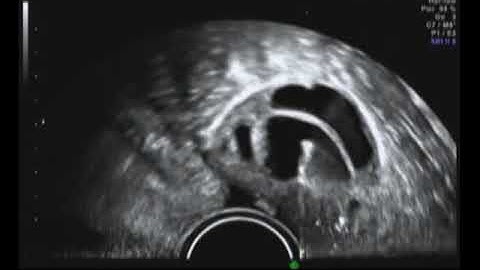

IVF Explained: How the egg retrieval process works